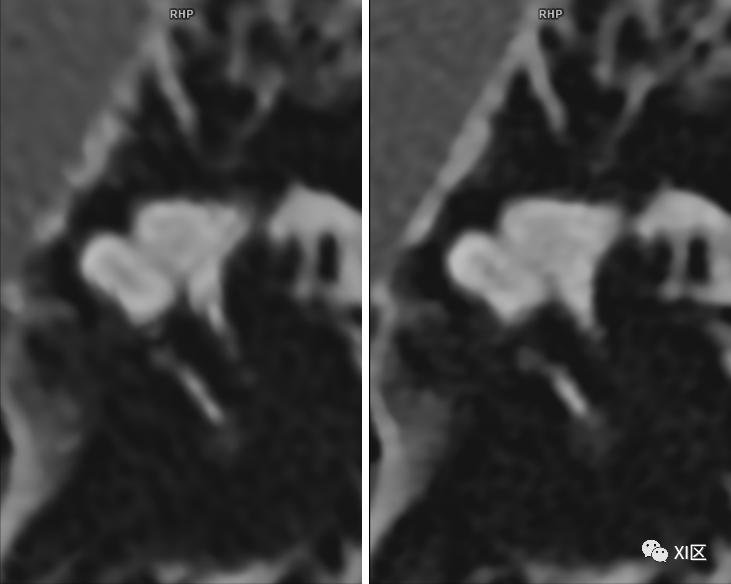

ZUHR和第三代双源UHR技术比较。第一代双源(A),第二代双源(B)和第三代双源(C)内耳图像比较。注意使用0.4x0.5 mm的小焦点第三代双源UHR模式图像质量显著改善。层厚均为0.4 mm。

Initial results of a new generation dual source CT system using only an in-plane comb filter for ultra-high resolution temporal bone imaging[J]. European Radiology, 2015, 25(1):178-185.

SOMATOM Force CT常规扫描重建0.6 mm(192x0.6 mm)图像(左)与IVR重建0.6 mm(576x0.6 mm)图像(右)比较。使用IVR技术的图像内耳细微结构显示更清晰。